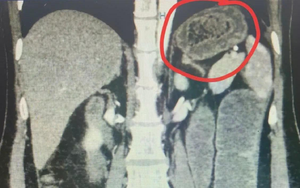

Người phụ nữ bụng "cứng như đá", bác sĩ sốc khi phát hiện bí mật "đáng sợ"

Bé trai 5 tháng tuổi nguy kịch vì ông cho "nếm thử" rượu bằng đầu đũa - Ảnh 2.